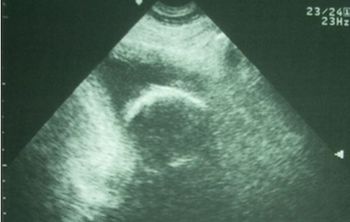

A 63-year-old man with hypospadias presents with ischuria x2 days but his bladder is barely enlarged. What do you see on the ultrasound?